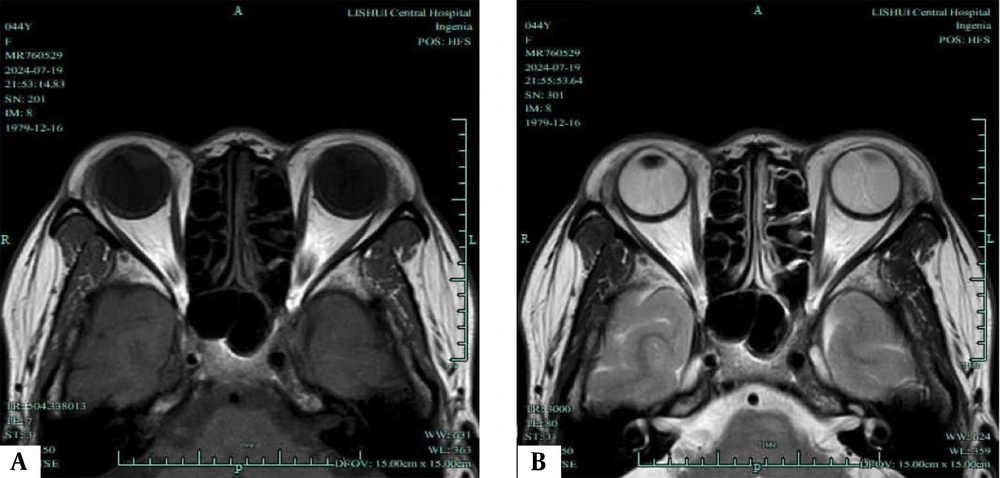

Likewise, as illustrated in Figure 4, the progression group exhibited significantly higher average EOM water fraction (0.96 ± 0.18 vs. 0.82 ± 0.15), average EOM water signal intensity (409.55 ± 115.72 vs. 330.86 ± 105.96), average EOM fat signal intensity (104.20 ± 13.88 vs. 80.26 ± 9.96), average lacrimal gland signal intensity (89.62 ± 11.32 vs. 79.38 ± 10.25), average of unilateral four EOM fat fractions (69.96 ± 9.15 vs. 51.80 ± 7.90), average EOM T2 value (81.75 ± 8.32 vs. 76.90 ± 7.14), and average EOM cross-sectional area (54.65 ± 7.88 vs. 42.50 ± 6.98) compared to the non-progression group. These differences were statistically significant (t = 3.711, 2.734, 8.858, 4.123, 9.290, 2.738, 7.116, P < 0.05).